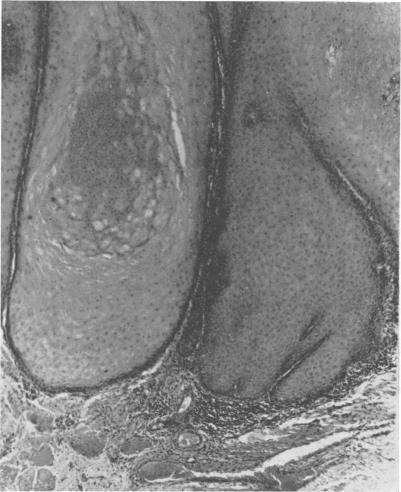

Gian keratoacanthoma on the inner surface of the prepuce was observed in a 45-year-old man. First symptoms had appeared three months earlier. The tumour was surgically removed. The main histological features of the tumour were enormous, but relatively regular, acanthosis of rete pegs revealing no similarity to the squamous-cell carcinoma, and an exclusively parakeratottic eleidine-containing central plug. The name parakeratoacanthoma is suggested for this type of tumour.